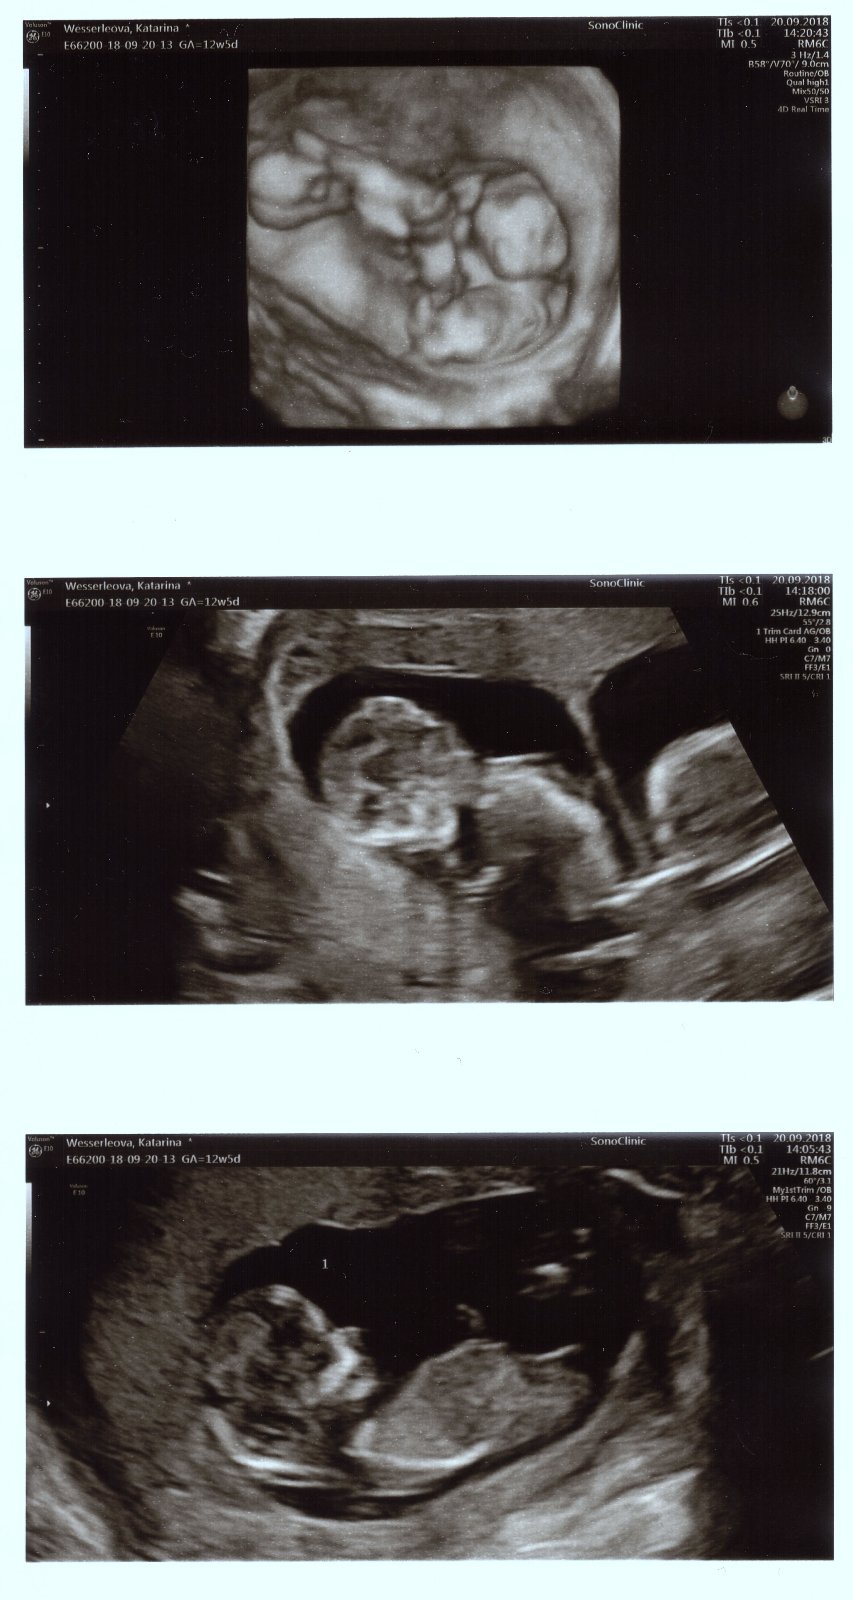

Ahojte baby, tak dnešný ultrazvuk dopadol dobre, všetko je v poriadku, doktorka pomerala všetko a detičky vyzerajú zdravé, zobrali krvičku a výsledok bude o týždeň, objednala som sa už aj v 20tt na morfologický. Detičky krásne podrástli, hýbali sa o sto šesť, manžel bol nadšený a na 80% to vyzerá na dievčatká.

1 obrázok sú obidve spolu, 2 obrázok jedno bábätko a 3 obrázok druhé bábätko

@babikadaska videla na utz, že sú na 80% dievčatká, aj nám to ukázala a vysvetlila a o výsledky mám volať o týždeň